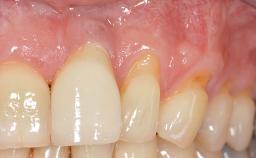

Early Implant Placement, Contour Augmentation, and Autologous Connective-Tissue Graft Using a Tunneling Technique to Replace an Upper Incisor with Generalized Gingival Recession

Variations in soft-tissue volume, evidenced either by an overabundance (Evian and coworkers 1993; Levine and McGuire1997; Dolt and Robbins 1997) or by a deficiency of soft or hard tissue can complicate implant-supported rehabilitations in the esthetic zone (Lorenzana 2008; Lorenzana and coworkers 2009). The present case illustrates the replacement of a failing upper left lateral incisor complicated by generalized severe gingival recession in the esthetic zone.

| Soft Tissue Contour and Volume | Significantly deficient |